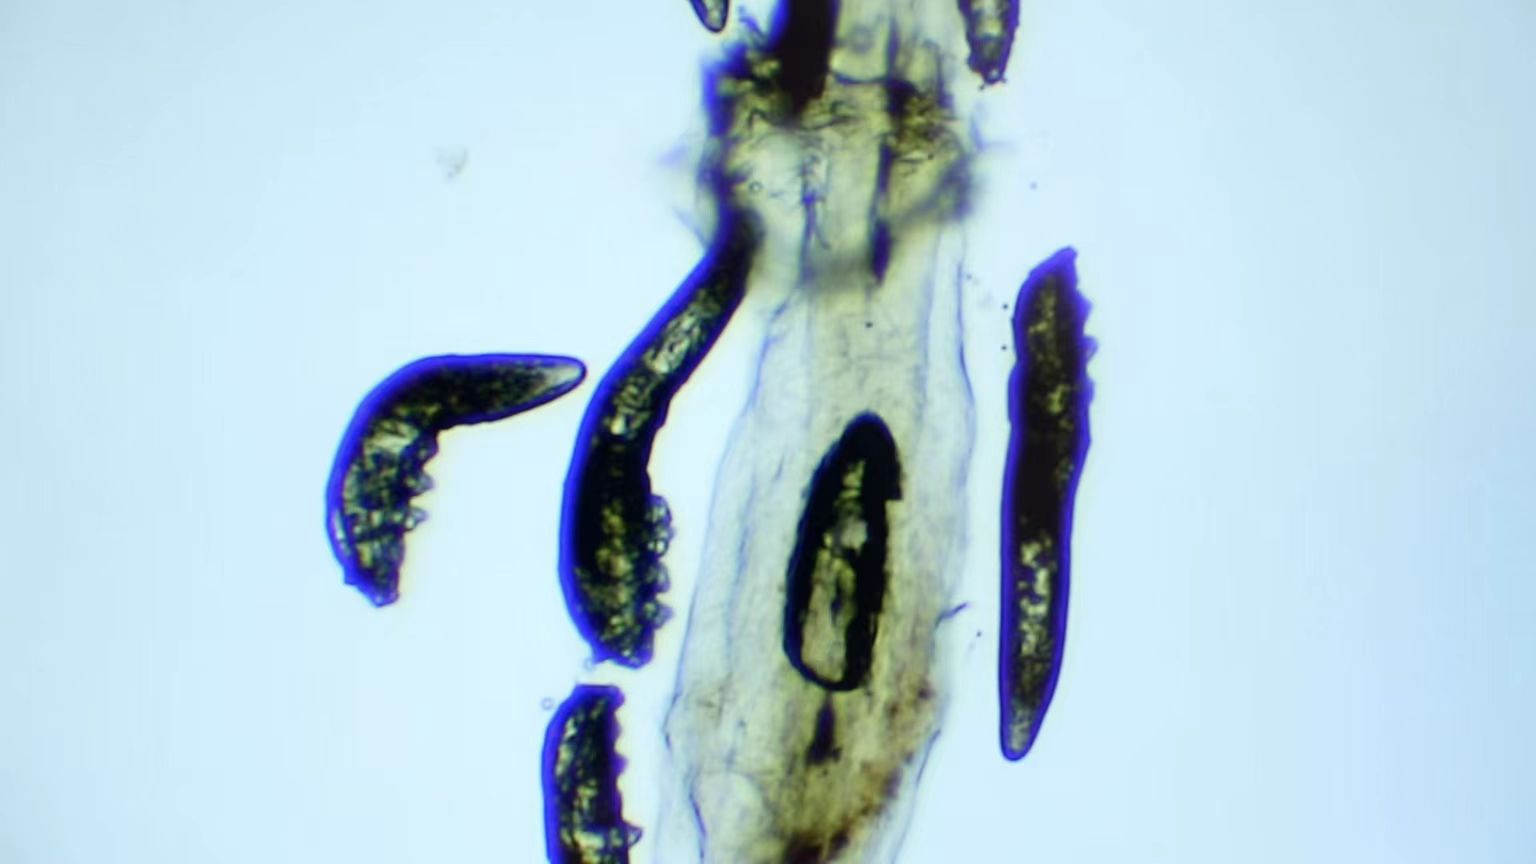

我院开设有干眼特色门诊,可通过在显微镜下检查拔取的睫毛,有效判断是否存在过量蠕形螨。